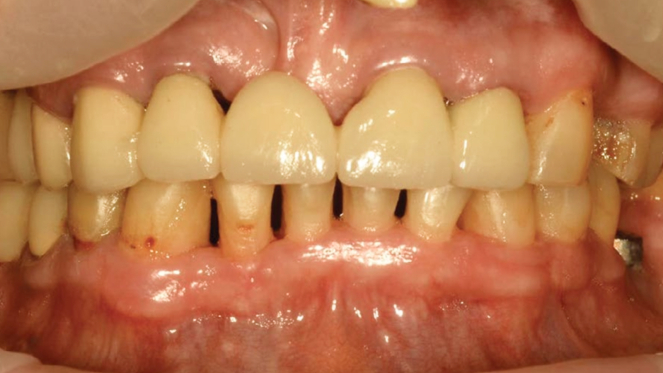

Хронический пародонтит средней степени тяжести

Результат через 2 недели

Вектор терапия по схеме, затем ФДТ 2-3 раза в неделю Сочетание периоскан, вектор-терапии и ФДТ 2-3 раза через неделю.

Параметры изменяются в зависимости от процедуры